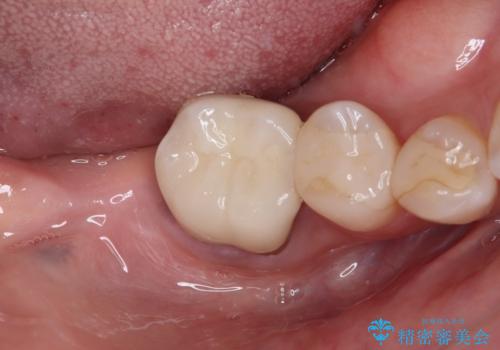

放置した奥歯 部分矯正を併用したインプラント補綴治療

- 右下欠損部のインプラント治療を希望して来院された患者様です。

右下の欠損部を長期間欠損を放置していたことで、咬み合う上の奥歯が動いてしまっていたので、まずは上顎奥歯の部分矯正を行うこととしました。

理想的な咬み合わせに改善した上で、インプラント補綴治療を行うこととしました。